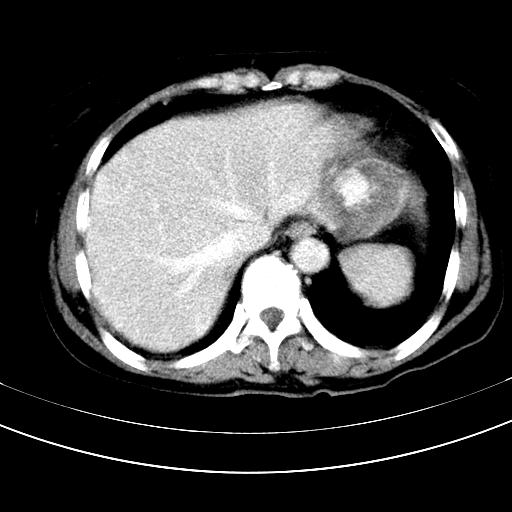

补充强化片

肝左叶及尾叶低密度灶,增强有渐进性明显强化,考虑血管瘤。胃内“充缺”首先要排除异物(食物),变换体位可鉴别。增强时机抓的不好,还应该有延时像。

谢谢楼主的增强片子,平扫没发现左侧肾上腺的问题很不好意思,可惜片子只有门脉期,所以还只有猜,肝脏的病灶在门脉期部分强化,首先考虑为血管瘤(其他的用一种病不好解释)胃要喝水就好了现在不好说是否有问题,左肾上腺的问题考虑是肿瘤。

做了增强后,可以明确胃是没有肿瘤的,肾上腺也没有肿瘤.肝左叶的病灶首先考虑血管瘤,应该再延迟,肝尾状叶的病灶仍不能排除肝癌的可能性.